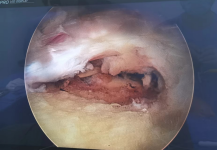

运动医学:肩袖损伤、肩关节脱位、钙化性肌腱炎、膝关节前后交叉韧带损伤、内侧副韧带损伤、内外侧半月板损伤、复发性髌骨脱位、髋关节撞击综合征、肘关节僵硬、慢性踝关节不稳等疾病的微创关节镜手术治疗。